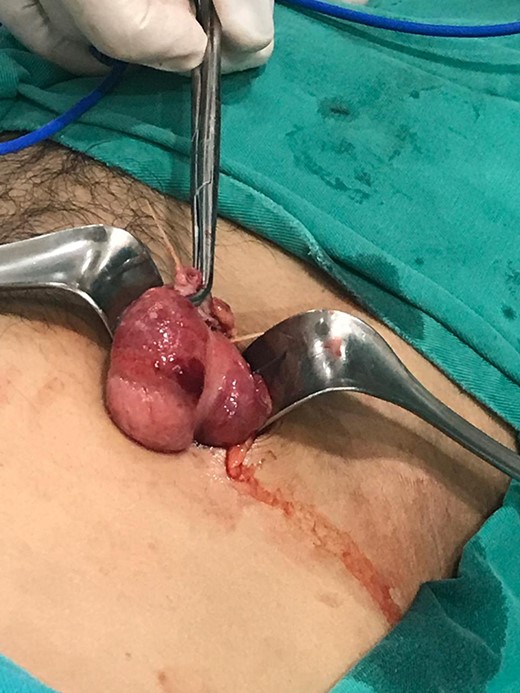

Surgery was straightforward from this point. The toothpicks were carefully removed, an appendectomy was performed, and the perforation at the base of cecum was repaired with an absorbable suture and covered with an omental patch. An extensive washout with saline solution was carried out and the remainder of the procedure was completed without complications (Fig. 4).